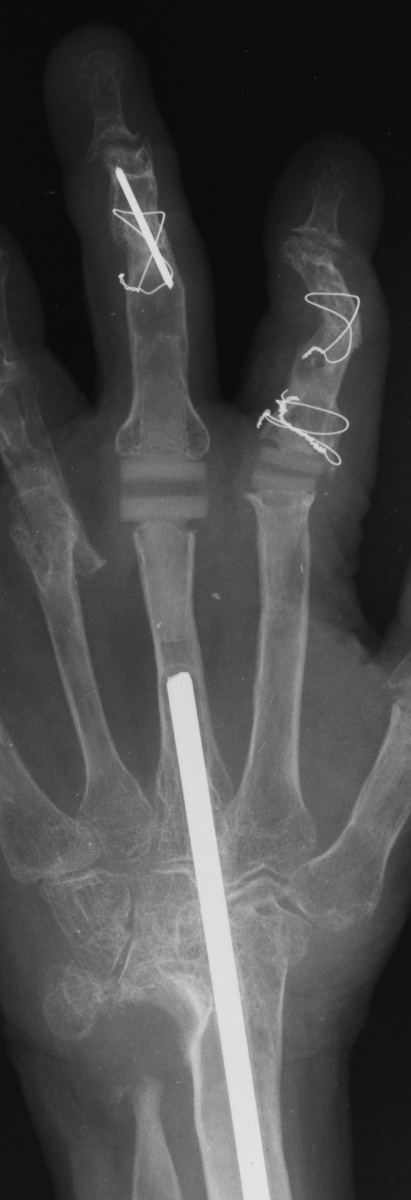

Her greatest desire was pinch reconstruction. This was approached in two stages: wrist fusion, implant removal and fusion of the index and middle PIP joints, followed by index and middle MCP arthroplasties. There are several alternative approaches, including index MCP fusion and revision PIP arthroplasties.

Below are xrays after the first set of reconstructions.

For the second stage of her reconstruction, the index proximal phalanx did not have adequate dorsal cortex to support an implant arthroplasty, and bone graft from the metacarpal head was used to reconstruct this.